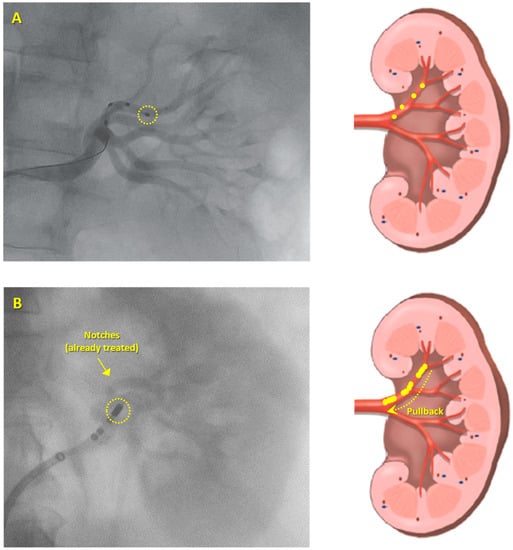

The acute procedures pre- and post-RDN, as well as, anticoagulation, analgesia and anesthesia techniques, were described previously [15]. Angiography of the aorta and renal arteries was performed using an 8-Fr Balkin introducer, and a 7-Fr standard irrigated cardiac ablation catheter was inserted (AlCath Flux eXtra Gold Full Circle 270°; VascoMed GmbH, Binzen, Germany) into the renal artery, allowing RF energy delivery to the renal artery. The catheter was then irrigated, and the length of its gold-tipped electrode (3.5 mm) was approximately four-fold higher than the electrode length (1 mm each one) of the catheter used in SPYRAL HTN-OFF and ON-MED, as shown in Figure 1. RF applications were performed within the renal arteries, bilaterally; a series of RF pulses at 8 W power for 60 seconds each were applied with an irrigation flow rate of 17 mL/min and an aim of >4 RF applications per renal artery, depending on their length. We started circumferential treatment distally and pulled the catheter back towards the proximal renal artery segment (Figure 1). The number of lesions per artery was based on the artery length.

Figure 1. Types of renal denervation approach used. (A) Symplicity Spyral multielectrode renal denervation (RDN) catheter (Medtronic, Galway, Ireland) which allows simultaneous or sequential energy treatments into a left renal artery (each one out of four electrodes is 1 mm in length). (B) 7-Fr standard irrigated cardiac ablation catheter with a 3.5 mm electrode tip length (AlCath Flux eXtra Gold Full Circle 270°; VascoMed GmbH, Binzen, Germany) was inserted into a left renal artery and was moved in a circumferential pullback fashioned from the distal to the proximal renal artery segment. Yellow dots represent ablated spots.